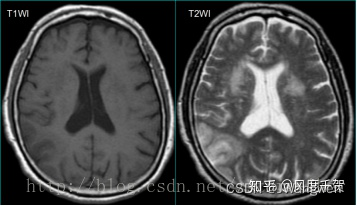

如下图所示,左:T1加权图像 右:T2加权图像

T1加权突出显示解剖结构,T2加权则能够突出显示病灶